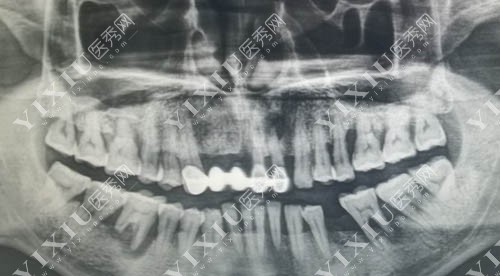

口腔修复治疗ct